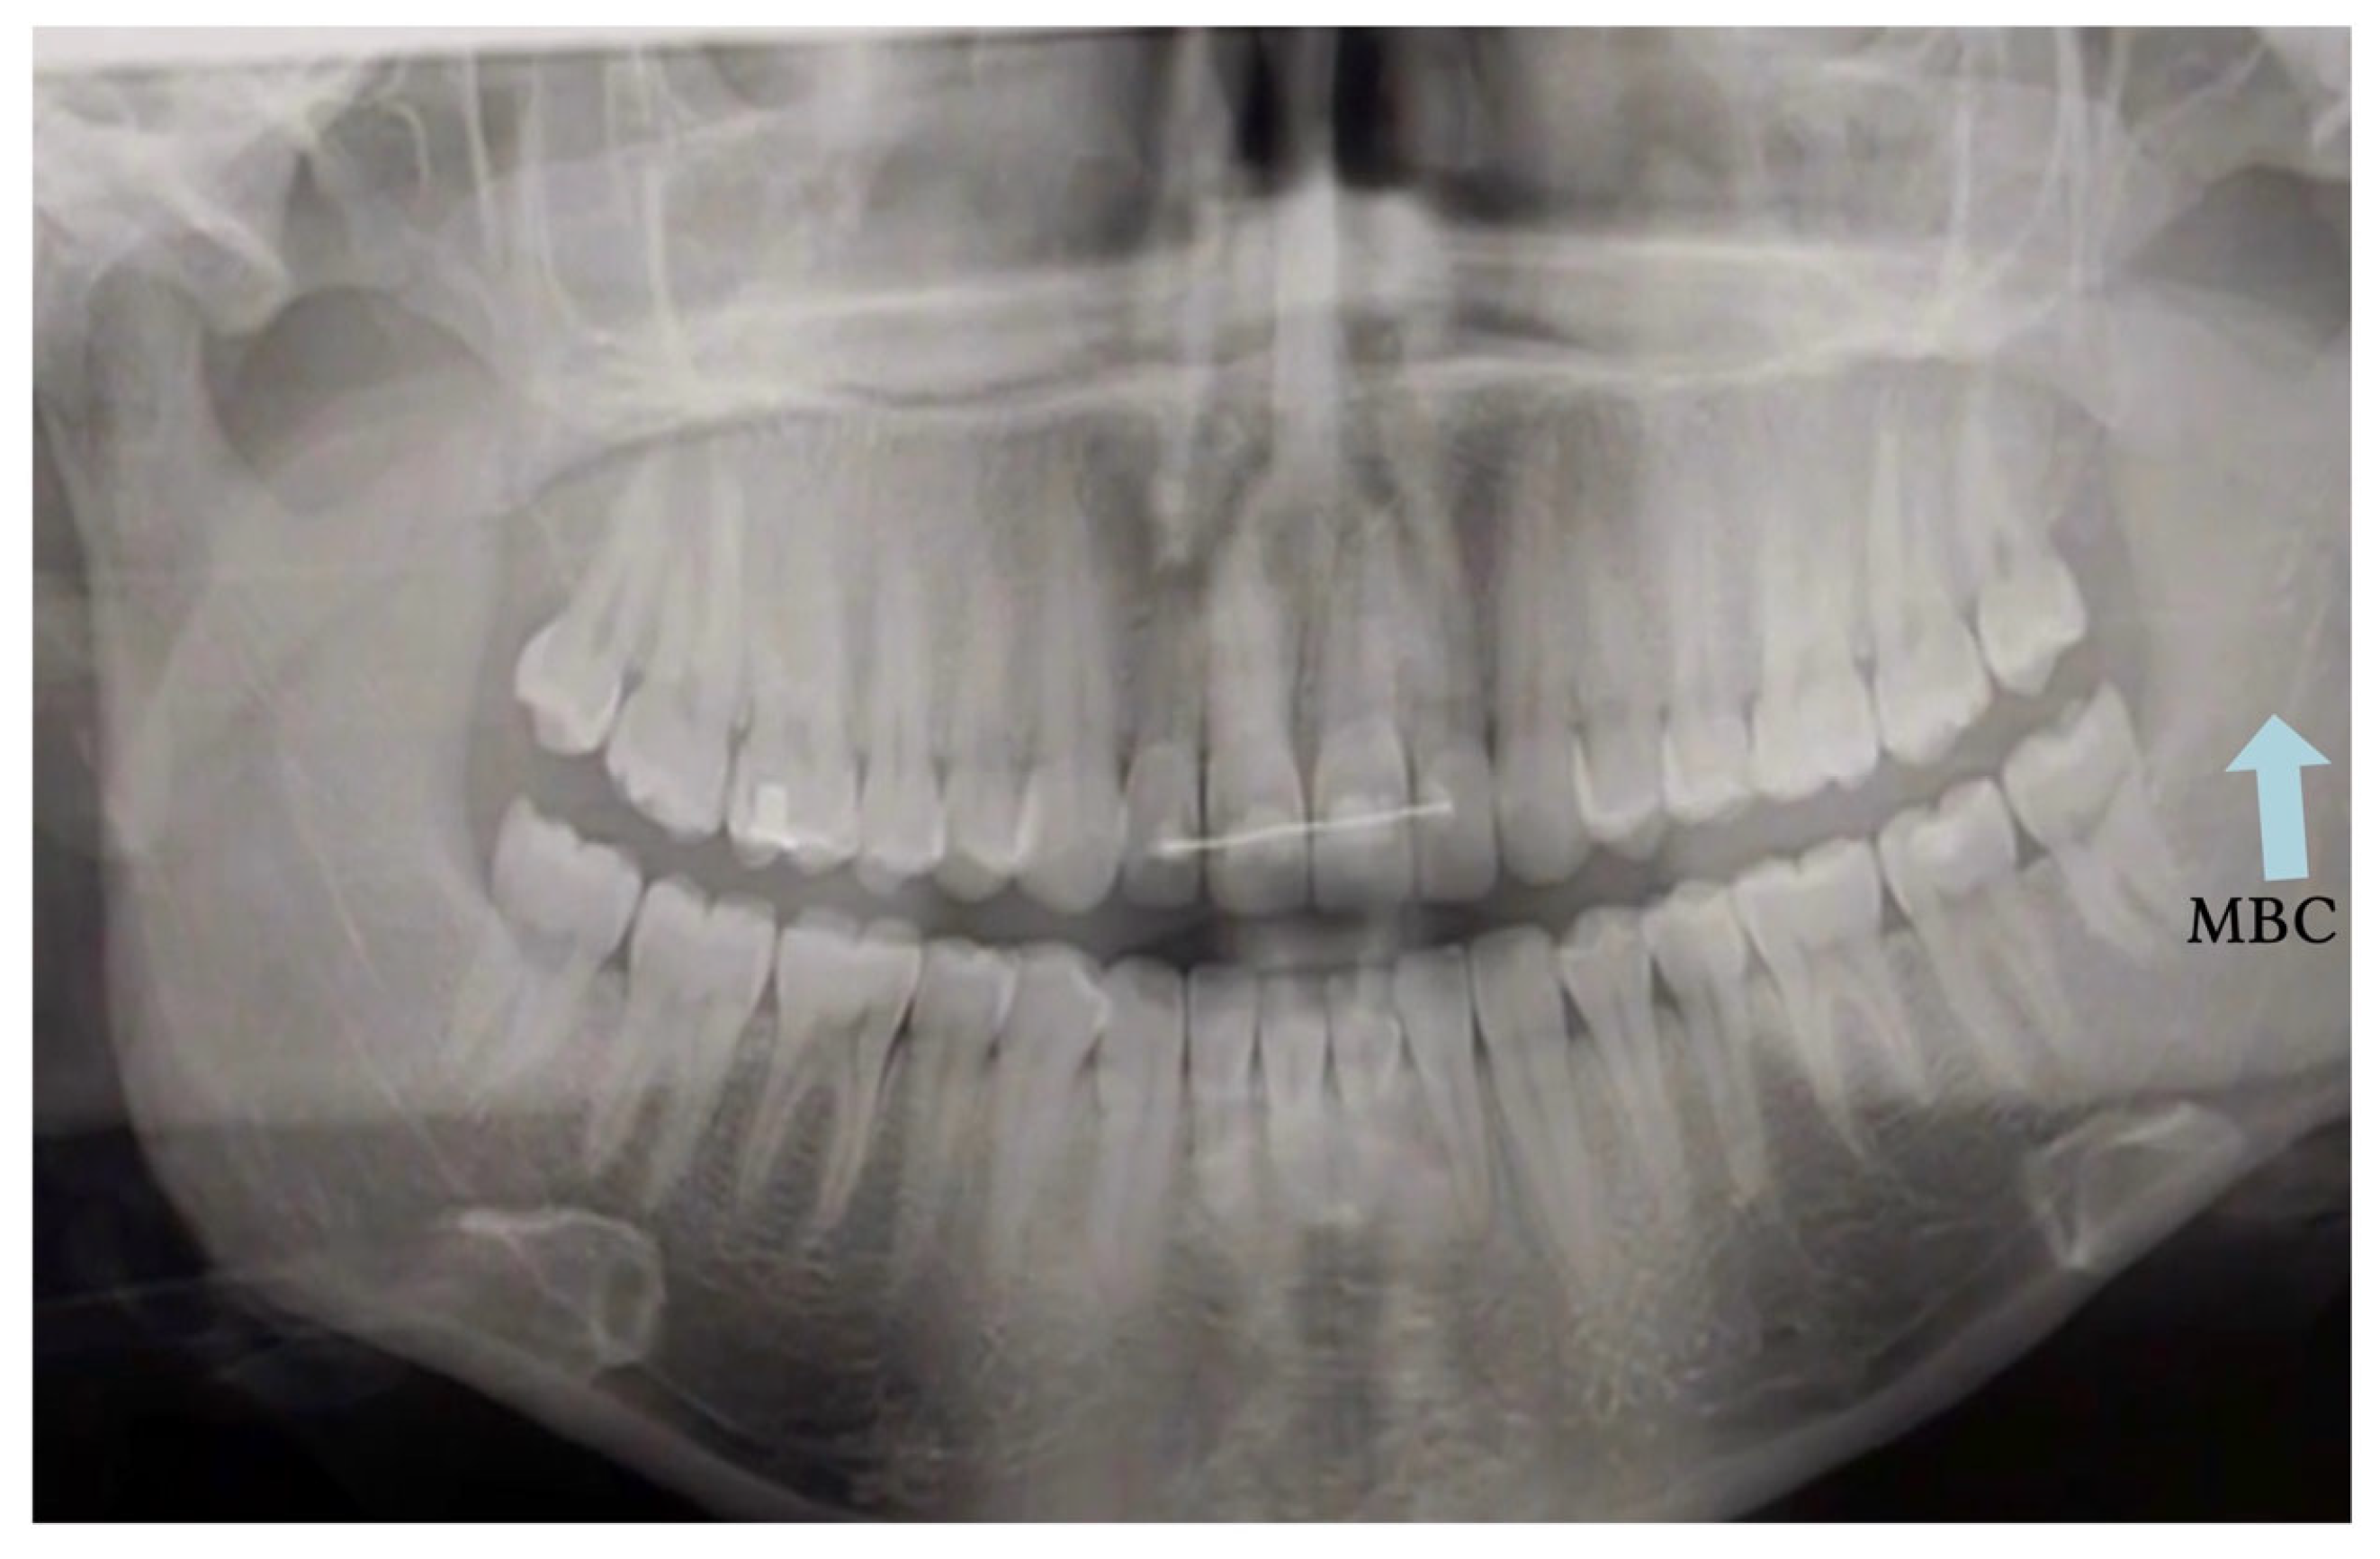

Traditional PR has significant limitations in accurately detecting MC anatomical variations. Earlier studies relying exclusively on panoramic imaging reported very low prevalences typically below 1% for bifid MC, largely due to anatomical superimposition and the inherent distortion of two-dimensional imaging [4,5]. Figure 5 illustrates why PR can be equivocal for canal variants; in such scenarios, CBCT confirmation is recommended if it would alter the treatment plan.

Figure 5. Panoramic radiograph (PR) showing a suspected bifid mandibular canal (BMC; blue arrow). The blue arrow indicates the cortical outline suggestive of canal duplication. PR alone cannot confirm this finding; CBCT is recommended when confirmation would change management (CBCT not shown).